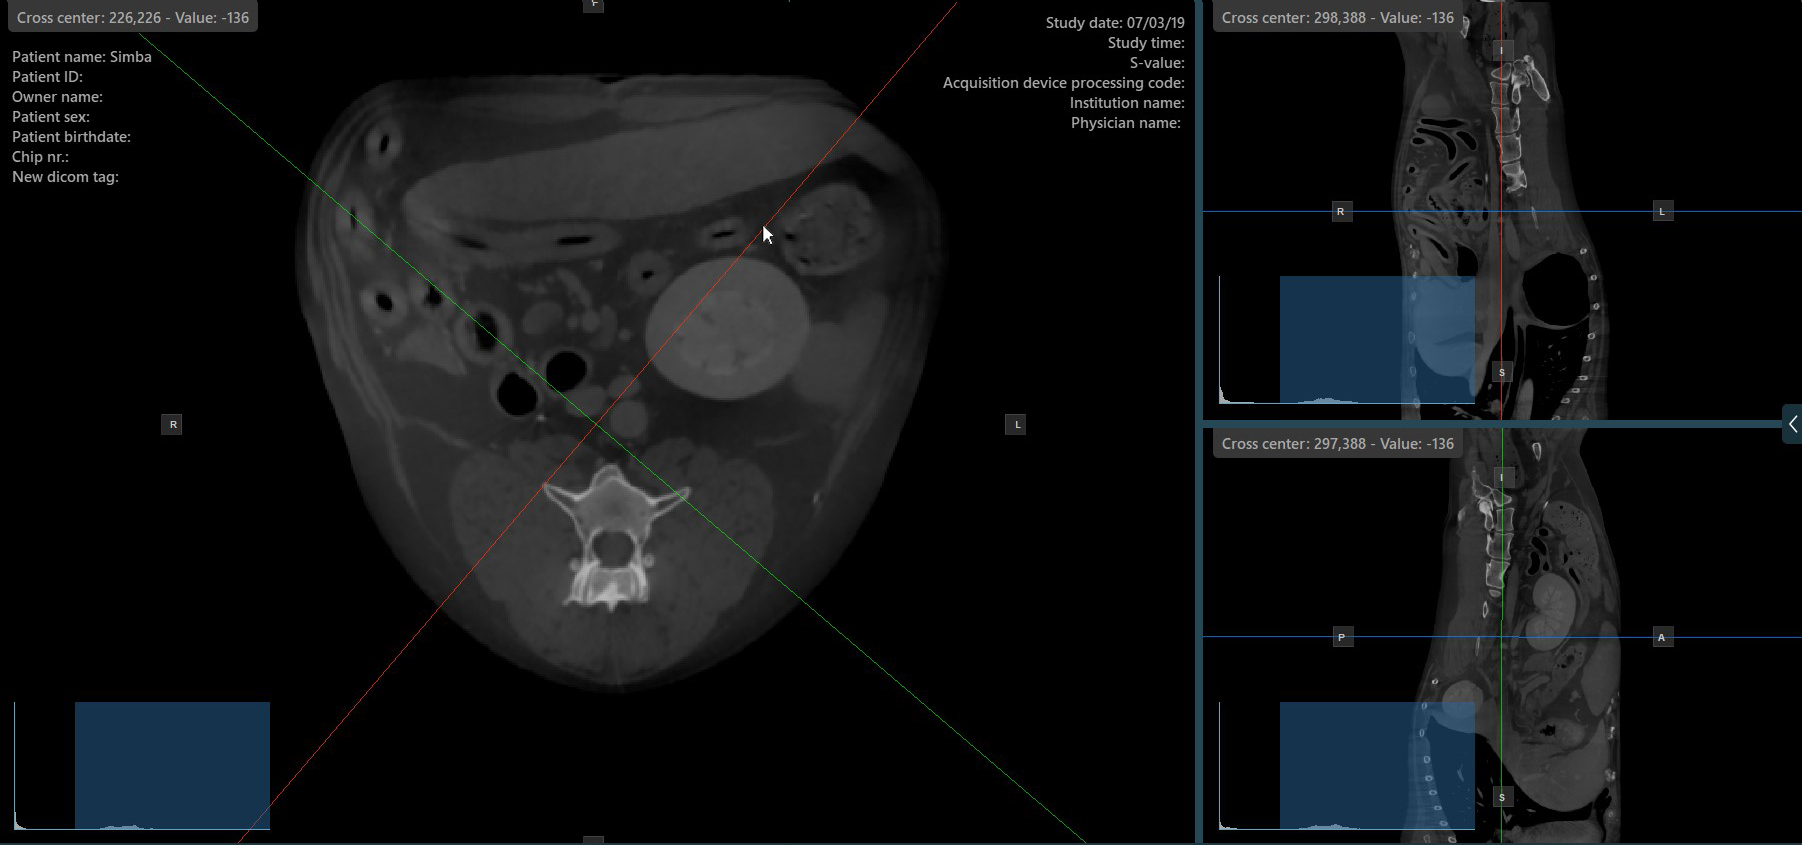

Drücken Sie das Symbol Senkrechte Slicer

in der linken Werkzeugleiste, um die gleichzeitige Rotation der Slicer zu aktivieren. Unabhängig von ihrer vorherigen Orientierung werden die Slicer so neu ausgerichtet, dass sie senkrecht zueinander stehen.

Schalten Sie die Option Senkrechte Slicer

um, um den aktiven Modus der Slicer jederzeit zu wechseln, oder wählen Sie eine der Optionen Werkzeuge -> Senkrechte Slicer

oder Werkzeuge -> Getrennte Slicer

im CT-Viewer-Menü.